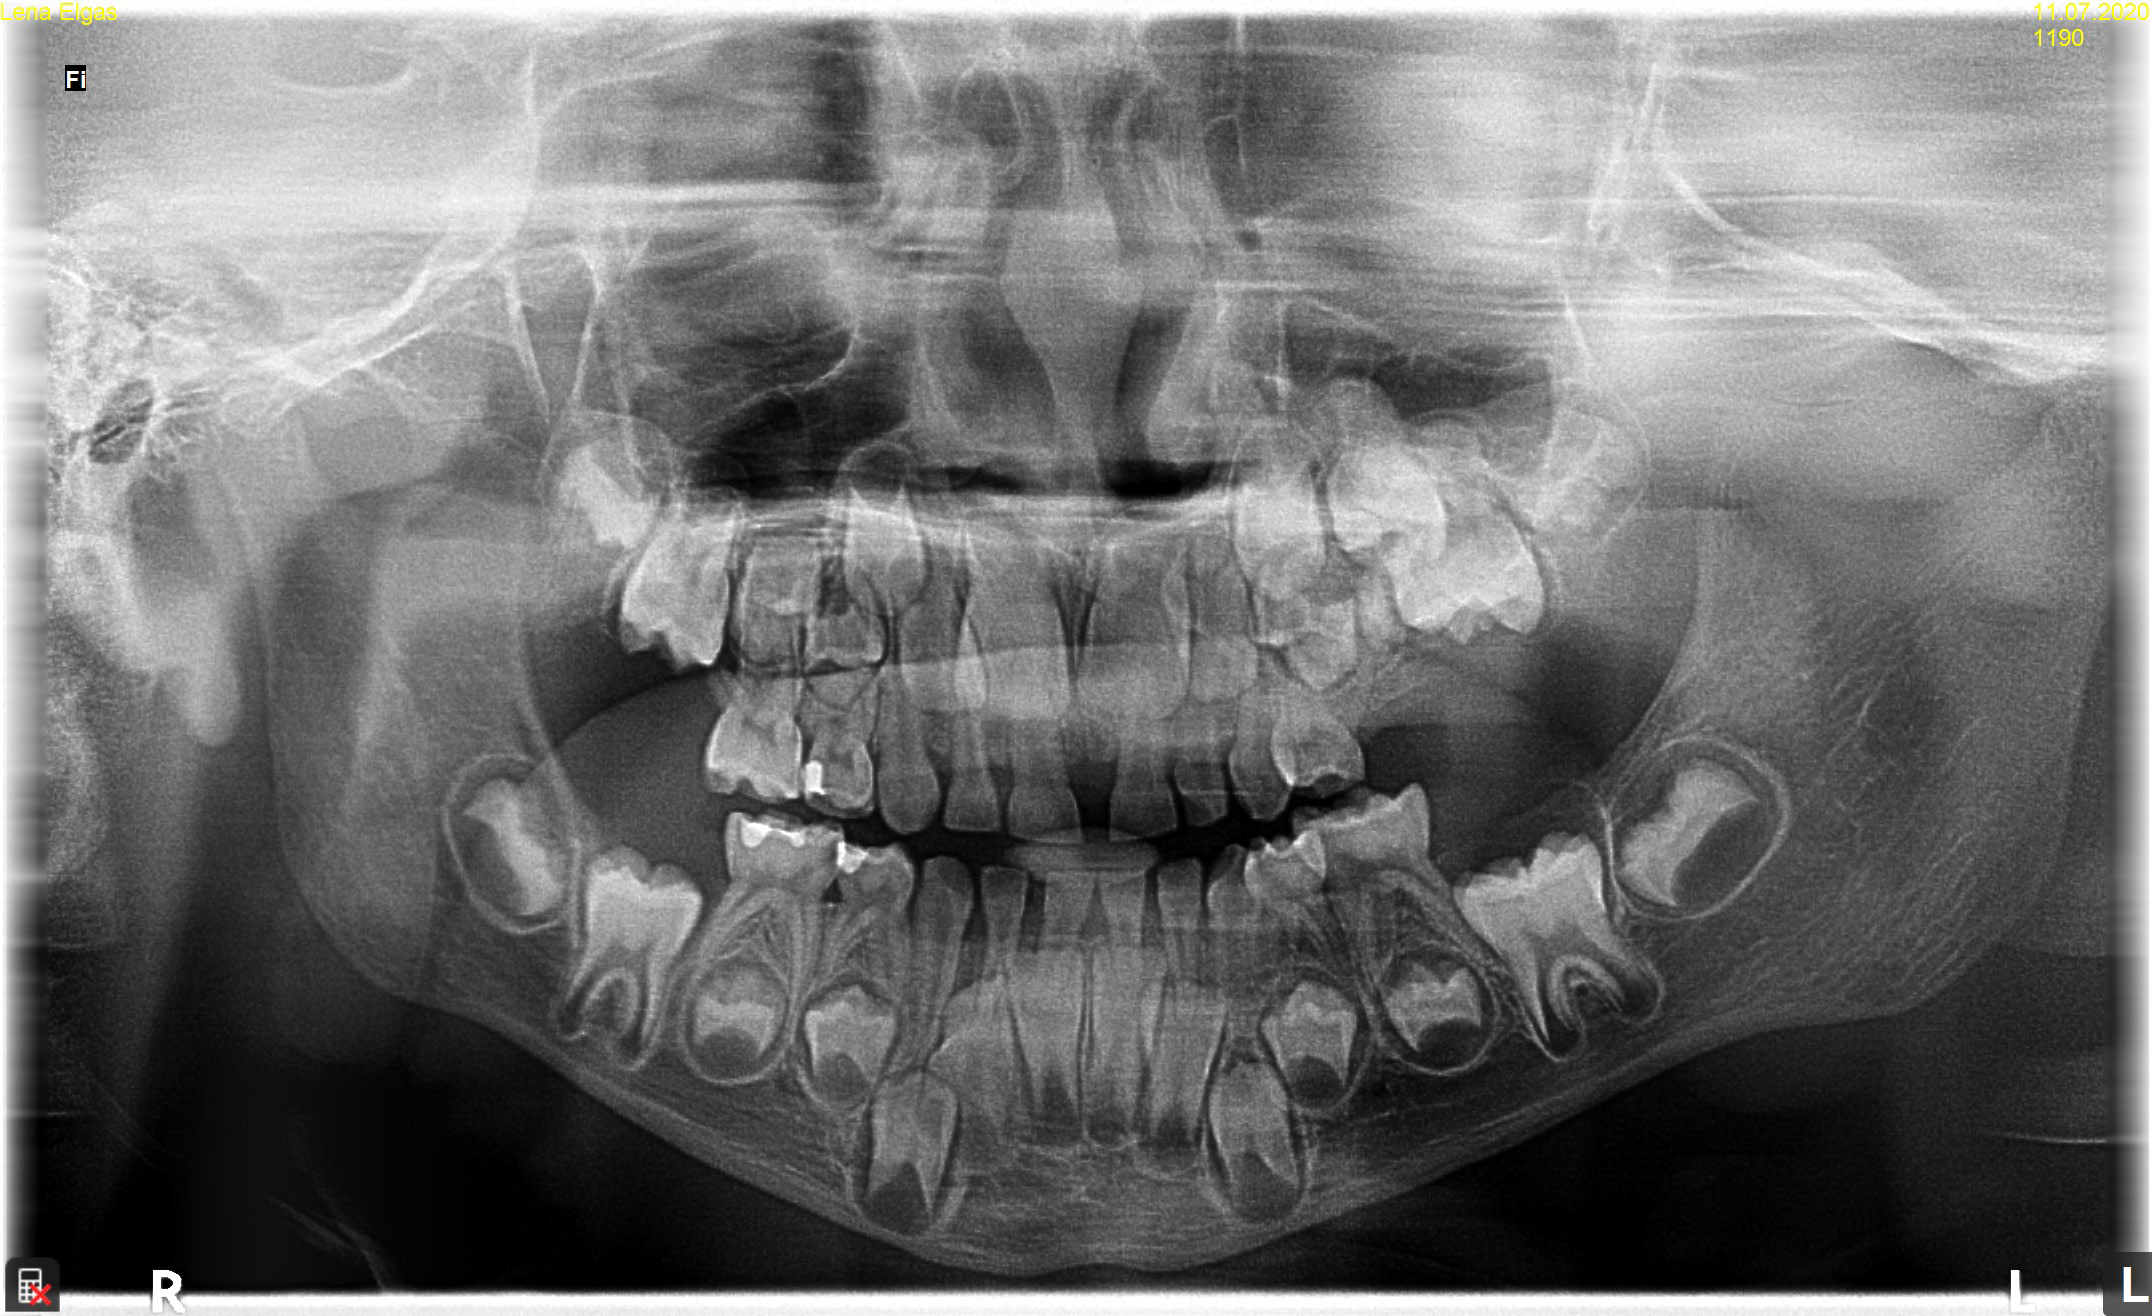

A total of 20 patients (13 (65%) boys and 7 (35%) girls), aged between 2.8 and 17.6 years (mean age: 8.96 ±4.20 years), were included in the study. The study involved general and local history-taking concerning chronic comorbidities and the medications received, dental history (the reason for the visit, presenting complaints), and extraoral (facial symmetry and lymph nodes) and intraoral (the number and type of erupted teeth, the assessment of the shape and consistency of the alveolar process) clinical examination. All patients underwent radiological and histopathological examination. Depending on the indications, tooth X-rays, panoramic radiography, CBCT and/or CT were performed. Radiological imaging was used to assess the location and type of odontoma, the presence of impacted or retained teeth, gaps, and tooth displacement. While OCp were found in X-ray images as high-density radiopacities arranged as numerous small deformed denticles (odontoids) surrounded by a band of radiolucency with an osteosclerotic border, OC were characterized by irregular radiopacities with a radiolucent edge and an osteosclerotic rim. The treatment of choice for all patients was the enucleation of the tumor with the capsule surrounding it.

The patients had the following examination performed: tooth X-ray (11 (55%)); panoramic radiography (11 (55%)); CBCT (12 (60%)); or CT (1 (5%)). X-ray images revealed 18 OCp (of which 2 were described as erupted) and 2 OC.

In 11 patients (55%), odontomas occurred in the maxilla – 4 (20%) in the midline, 5 (25%) on the left side (Figure 2) and 2 (10%) on the right side, and they were all OCp, of which 1 (5%) on the right side was an erupted odontoma. Nine patients (45%) were diagnosed with lesions in the mandible, with 5 (25%) of them having lesions on the right side (including 4 (20%) OCp and 1 (5%) OC) (Figure 3), 3 (15%) of them with lesions on the left side (1 (5%) OCp, 1 (5%) OC and 1 (5%) erupted odontoma) and 1 patient (5%) with OCp in the area of incisors.

Radiographically, OC is a highly dense radiopacity of irregular shape, surrounded by a band of radiolucency with a sclerotic rim,6, 19 and OCp is a dense radiopacity arranged as numerous small deformed denticles (odontoids) surrounded by a band of radiolucency and a sclerotic rim.6 Similar radiological pictures were obtained for our patients. Histopathological examination should be conducted to confirm the clinical and radiological diagnosis. On microscopic examination, OCp is described as fragments of the dental pulp, dentin, enamel matrix, epithelium, and connective tissue, or as fragments of a tooth with preserved histological structure, with fragments of fibrovascular tissue. On the other hand, OC is described in histopathological findings as fragments of dentin and connective bone tissue. The histopathological picture of OC is very similar to that of an ameloblastic fibro-odontoma (AFO).20, 21 And this was the microscopic picture obtained for the lesions removed in our patients.